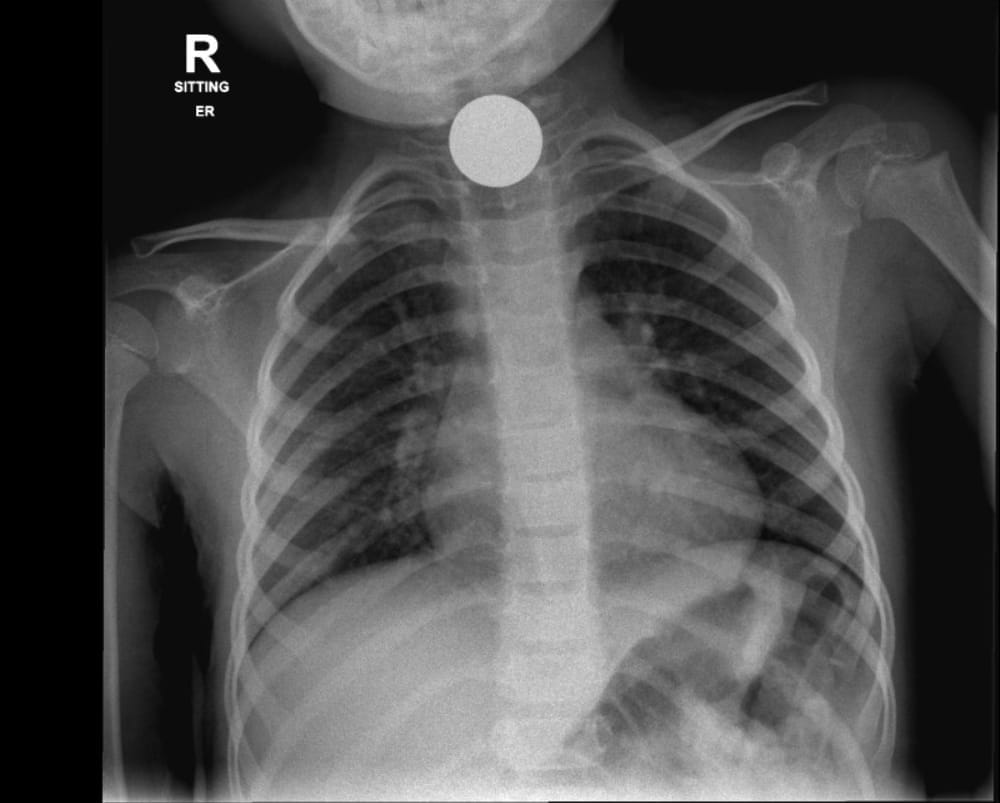

نقل 4 أطفال لمستشفى أشدود بعد ابتلاعهم قطع نقدية وأجواء ألعاب مغناطيسية

قدمت الطواقم الطبية في مستشفى " أسوتا " في أشدود، في الأيام الأخيرة، العلاج لأربعة أولاد، بعد أن ابتلعوا أجساما غريبة،

من بينها أجزاء لعبة " مغناطيس "، وقطع نقود. وقال متحدث بلسان المستشفى " ان اثنين من الأولاد الأربعة تم تسريحهم من المستشفى بعد ساعات من وصولهم اليها، لكم طفلتان ( 7 سنوات و 4 سنوات ) خضعتا لعمليات جراحية لانقاذهن ".

وفي التفاصيل، قال المتحدث بلسان المستشفى " أن الحديث يدور عن 4 أولاد، ابتلعوا أغراضا مختلفة، وانه لا علاقة بين الحوادث الأربعة".

تصوير: مستشفى " أسوتا " في أشدود